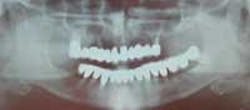

Radiograph of 71-year-old woman before and after implant restoration

Photos of same woman before treatment